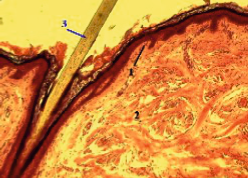

Верхний прочный слой кожи. Защищает организм от внешних воздействий. Клетки эпидермиса все время делятся, ороговевают и отпадают. Толщина эпидермиса на разных участках тела разная, варьируется от 0.02мм до 0.1 мм. Самый толстый слой эпидермиса на ладошках и подошвах - от 0.8м до 1мм.

Эпидермис состоит из нескольких слоев:

• Роговой слой

• Блестящий слой

• Зернистый слой

• Шиповатый слой

• Базальный слой

Мембрана тормозит все то, что проходит через эпидермис

Поэтому необходимо имплантировать пигмент чуть ниже эпидермиса - в сосочковый слой (самый верхний слой) дермы.

В сосочковом слое дермы проходит очень много капилляров, нервных окончаний, лимфатических протоков, сальных и потовых желез. Поэтому, если ты сработала правильно и имплантировала пигмент туда, куда нужно, то ты можешь увидеть маленькие капельки лимфы, что скажет о правильной работе.

Дерма

Волокна дермы состоят из коллагеновых и эластиновых частиц и волокон соединительной ткани. Коллаген и эластин отвечают за упругость нашей кожи, и чтобы в ней было достаточно влаги, а также за отсутствие морщин и чтобы минеральные и питательные вещества проходили в эпидермис. Толщина дермы примерно от 0.5 мм до 3 мм.

Как уже говорилось, в дерме находится много кровеносных сосудов,лимфатических протоков, нервных окончаний, потовых и сальных желез.

Гиподерма (подкожно-жировая клечатка)

Она образуется из пучков соединительной ткани дермы и жировых клеток. Это более рыхлый слой кожи, поэтому вводить пигмент туда ни в коем случае нельзя. На границе дермы и гиподермы находится сеть артериальных сосудов. Поэтому, если вдруг ты прошла в неверный слой кожи, ты увидишь капли крови, выходящие наружу, которые не останавливаются, если протереть область ватным диском.Это означает,что начала работать в гиподерме. Продолжать работать так категорически нельзя, тебе следует перейти на более высокий уровень, ближе к эпидермису.